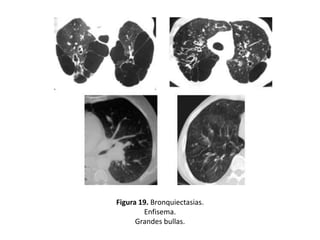

• Otros hallazgos demostrables mediante un estudio

con TAC y que pueden constituir signos indirectos de

BQ serían: (figuras 19-22).

– Enfisema

– Irregularidad de la pared bronquial

– Atelectasias

– Pérdida de volumen o áreas de consolidación

Figura 19. Bronquiectasias.

Enfisema.

Grandes bullas.